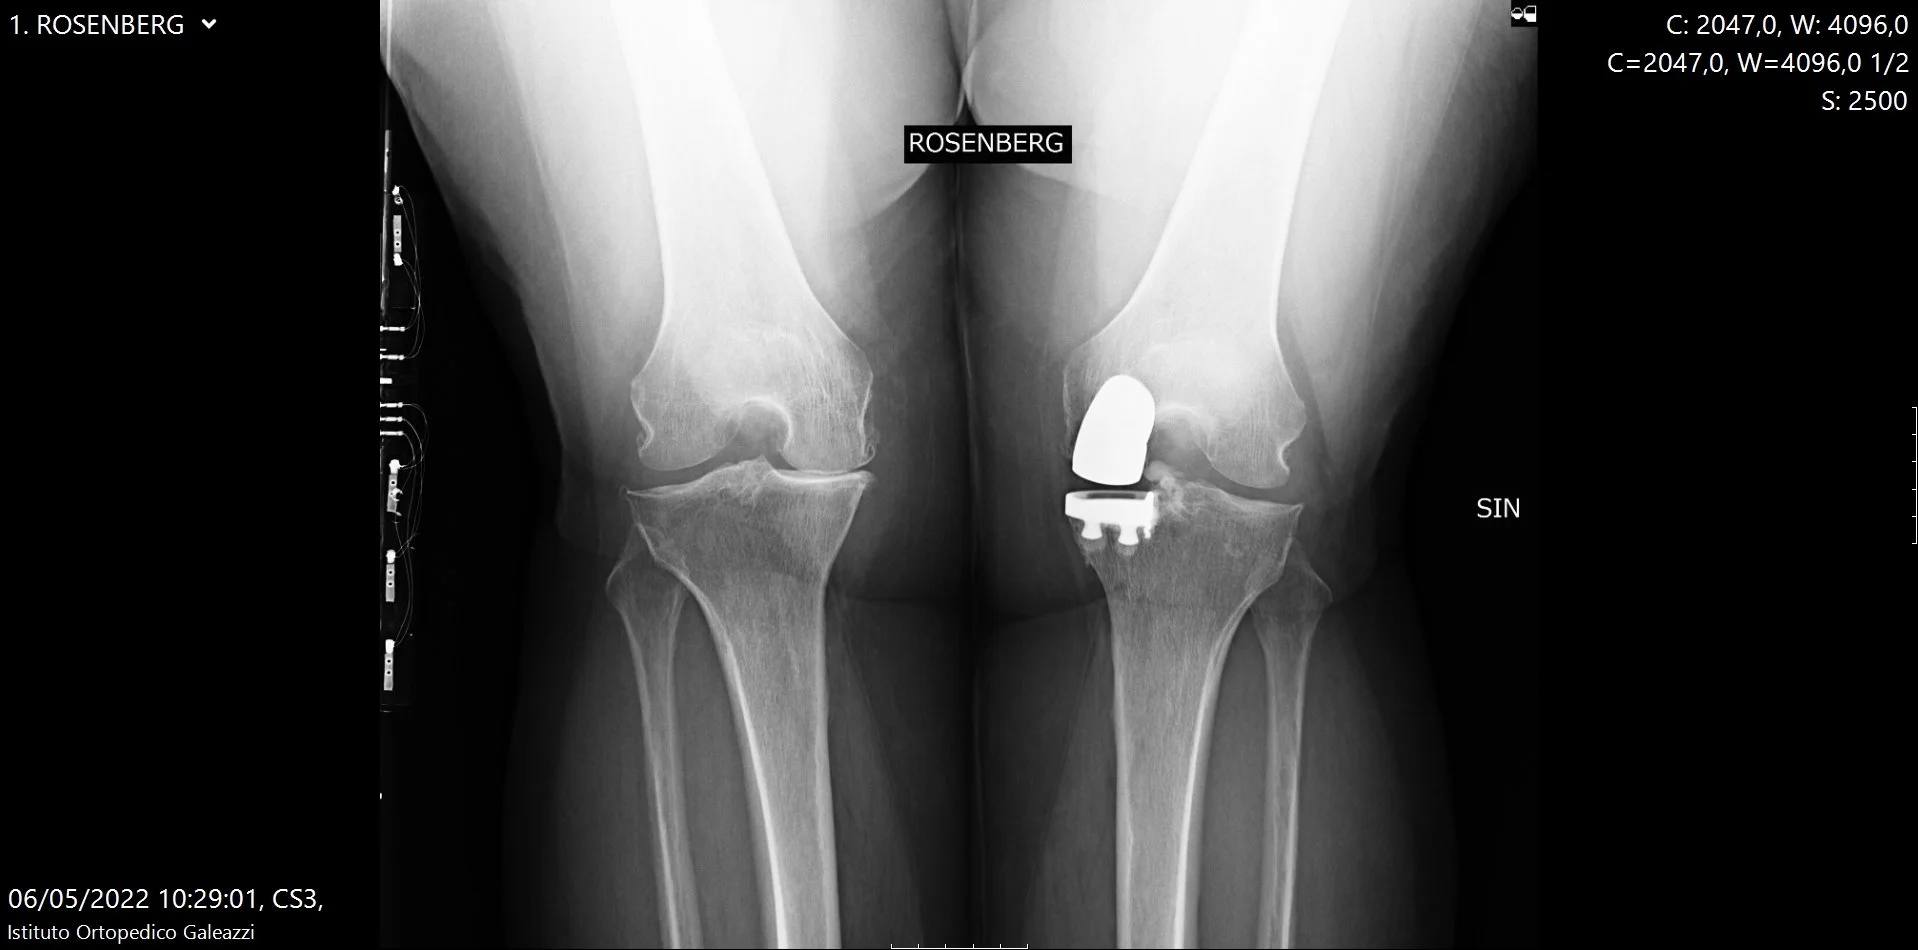

In questa guida chiara e completa spiego quali proiezioni eseguire (AP sotto carico, laterale, Rosenberg, assiale di rotula) e perché sono fondamentali per una valutazione corretta.